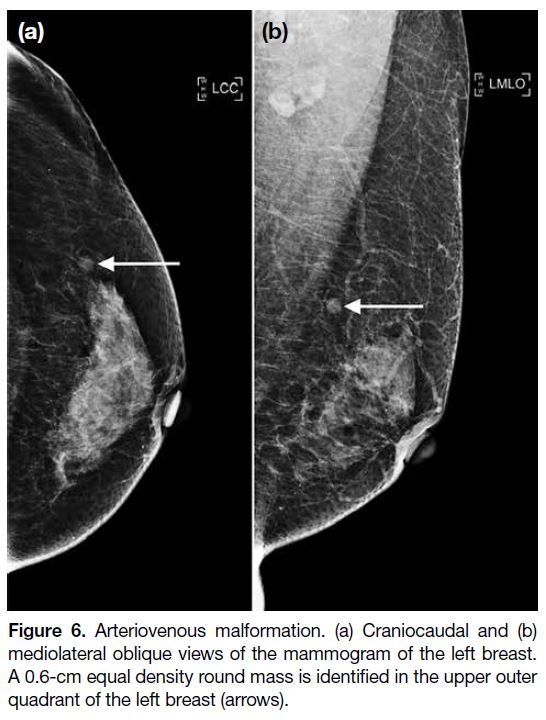

Arteriovenous malformations (AVMs) are exceedingly

rare in the breast, with only scant case reports. No specific

mammographic features are found in AVMs. Similar

to other benign vascular entities, they may present on

mammography as an equal density mass with a round

shape and circumscribed margins (Figure 6). They may

also contain benign-appearing calcifications, indicating

the presence of phleboliths.[7]

Figure 6. Arteriovenous malformation. (a) Craniocaudal and (b)

mediolateral oblique views of the mammogram of the left breast.

A 0.6-cm equal density round mass is identified in the upper outer

quadrant of the left breast (arrows).